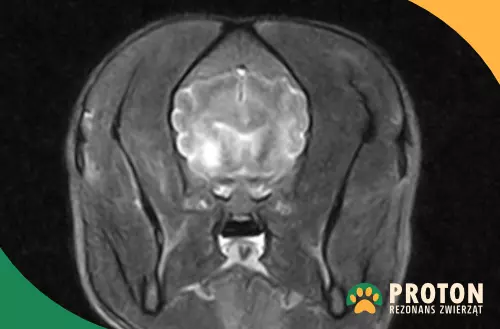

Obraz RM mózgu kota

Rezonans mózgu kota